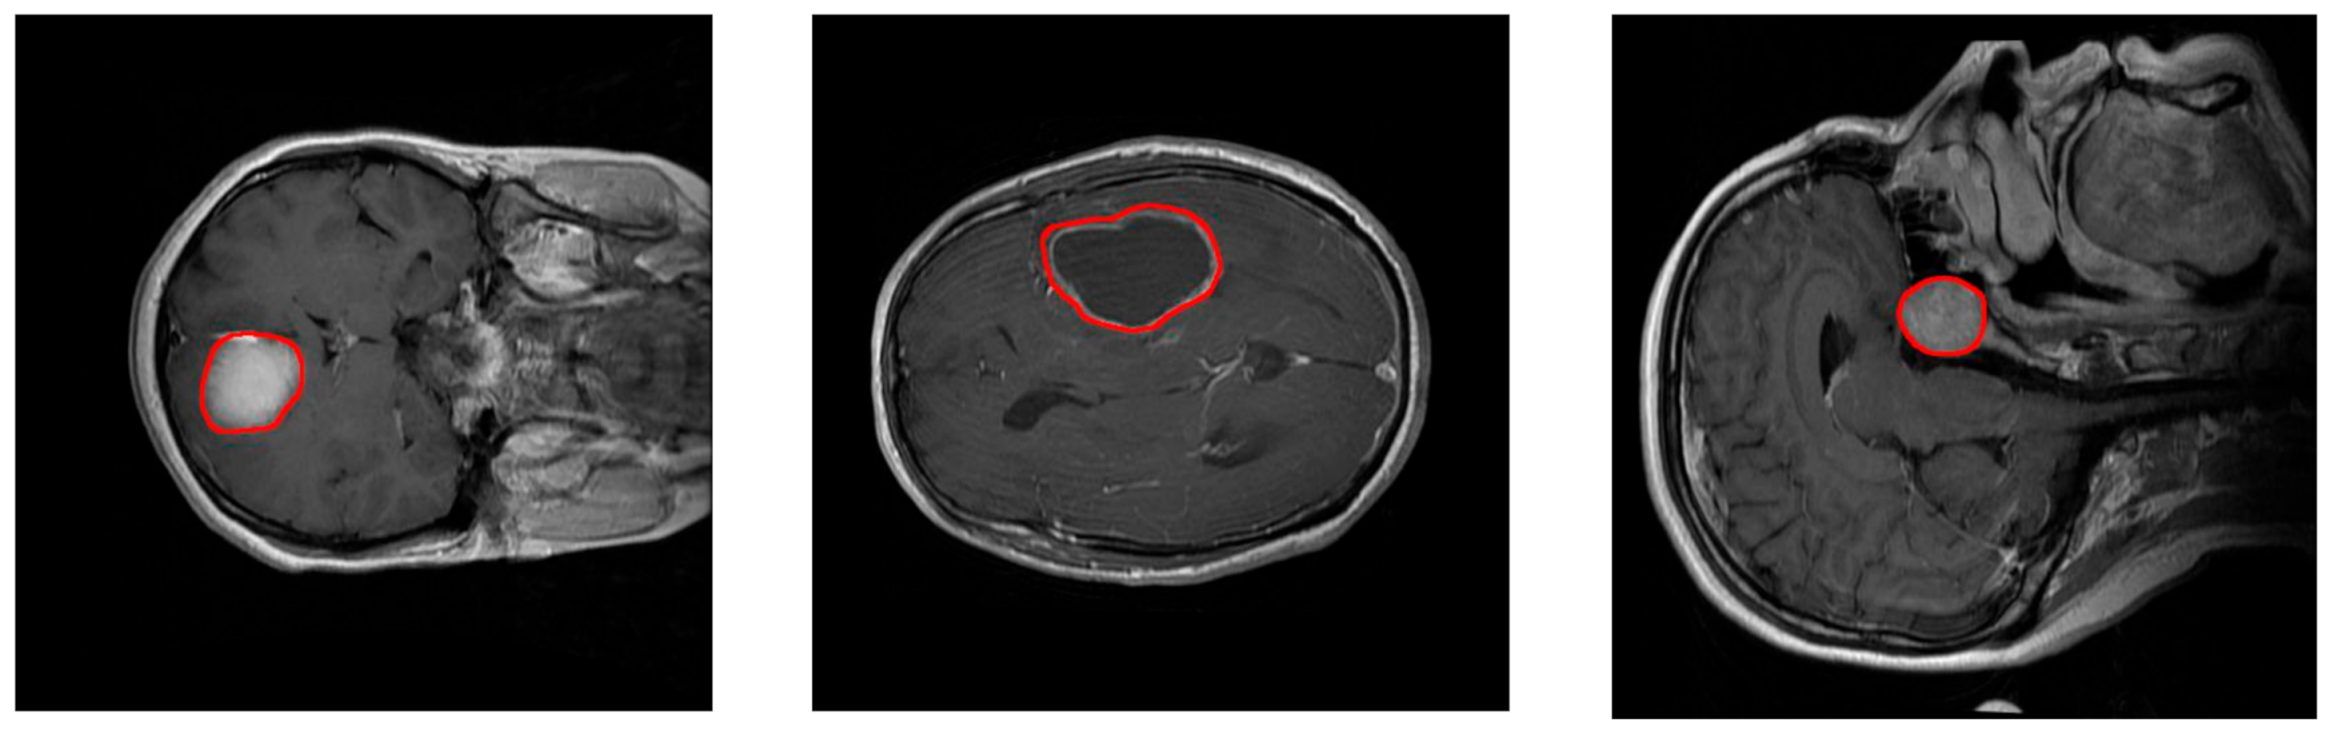

The aim of the work presented in this paper is to develop and test a Deep Learning approach for brain tumor classification and segmentation using a Multiscale Convolutional Neural Network. To train and test the proposed neural model, a T1-CE MRI image dataset from 233 patients, including meningiomas, gliomas, and pituitary tumors in the common views (sagittal, coronal, and axial), has been used [5]. Figure 1 shows examples of these three types of tumors. Additional information on the dataset is included in Section 2.2. Our model is able to segment and predict the pathological type of the three kinds of brain tumors, outperforming previous studies using the same dataset.

Figure 1.

Examples of MRI images of the T1-CE MRI image dataset. Left: coronal view of a meningioma tumor. Center: Axial view of a glioma tumor. Right: sagittal view of a pituitary tumor. Tumor borders have been highlighted in red.

This dataset contains 3064 slices and includes meningiomas (708 slices), gliomas (1426 slices), and pituitary tumors (930 slices) in the common views (sagittal, coronal, and axial). Figure 1 shows examples of these three types of tumors. This dataset provides also 5-fold cross-validation indices. By using this information, 80% (2452) of the images are employed for training and 20% (612 images) are used for obtaining performance measurements. The process is repeated 5 times.